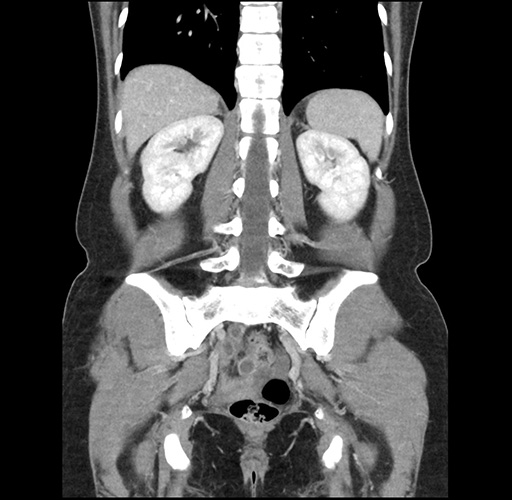

Imaging Analysis

Look through the patient's CT scan to identify any areas of concern for the necessary procedure.

Based on your CT findings, which issue(s) would give reason for "planned slowing down moment(s)" in this case?

Considering a standard left lateral sectionectomy procedure, what step(s) of the operation would you do differently in this case ?